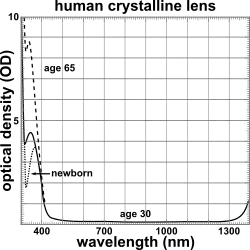

The lens blocks most ultraviolet light in the wavelength range of 300–400 nm; shorter wavelengths are blocked by the cornea. The pigment responsible for blocking the light is 3-hydroxykynurenine glucoside, a product of tryptophan catabolism in the lens epithelium.[60] High intensity ultraviolet light can harm the retina, and artificial intraocular lenses are therefore manufactured to also block ultraviolet light.[61] People lacking a lens (a condition known as aphakia) perceive ultraviolet light as whitish blue or whitish-violet.[62][63]